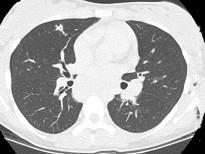

7岁,男,发热、消瘦,数月前触及颈部淋巴结肿大,CT和MR检查如图,请选择最可能的诊断 ( )A.淋巴瘤B.结节病C.淋巴结核...

问题 7岁,男,发热、消瘦,数月前触及颈部淋巴结肿大,CT和MR检查如图,请选择最可能的诊断 ( )

选项 A.淋巴瘤 B.结节病 C.淋巴结核 D.转移性淋巴肿大 E.胸腺瘤

答案 A